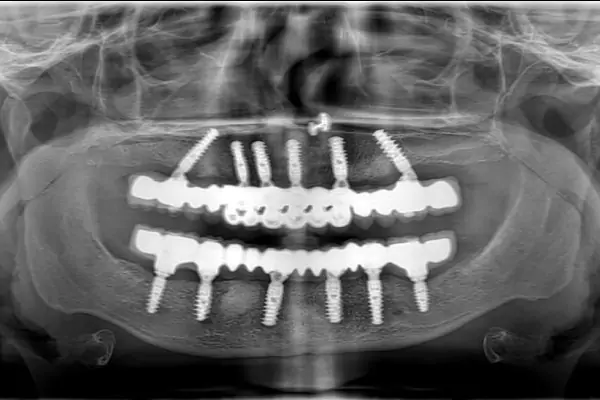

Full Mouth Dental Implants – Malo Titanium Bridge with Zirconia Crowns

Discover how full mouth dental implants using MALO titanium bridges and zirconia crowns can restore your smile with strength and aesthetic beauty.

Full Mouth Implants

Get a full arch restored using 4–6 implants for permanent teeth replacement.

When it comes to improving the condition of your teeth, knowing where to start can be confusing. At Smilex, though, we look to remove any uncertainty or confusion around the kind of dental care that you need. To do that, we provide a comprehensive service for full mouth rehabilitation in Pune. Full mouth rehabilitation is a highly individualized treatment.

The point of a full mouth reconstruction plan is to optimize the health of the entire mouth, including the teeth, the gums, and the bite. In many cases, it is necessary to replace or restore every tooth in the mouth using a combination of dental services. Our full mouth rehabilitation service in Pune offers the easiest way to get everything done at once.